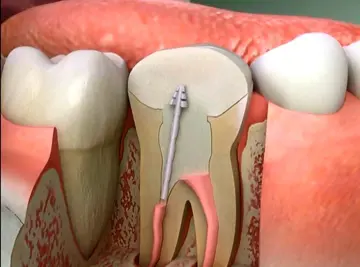

دندانپزشکی - صفحه 5